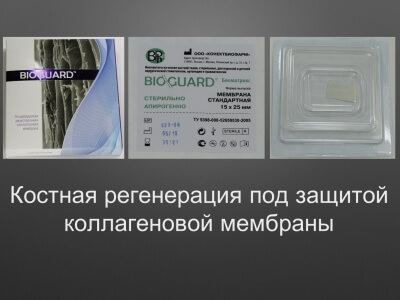

БИОМАТРИКС ФЛИС

З-D Матрикс с сохраненными прочностными характеристиками и повышенной гидрофильностью.

100% коллаген (1 -3 типов) животного (крупно-рогатого скота) происхождения.

АЛЬТЕРНАТИВА десневому трансплантату.